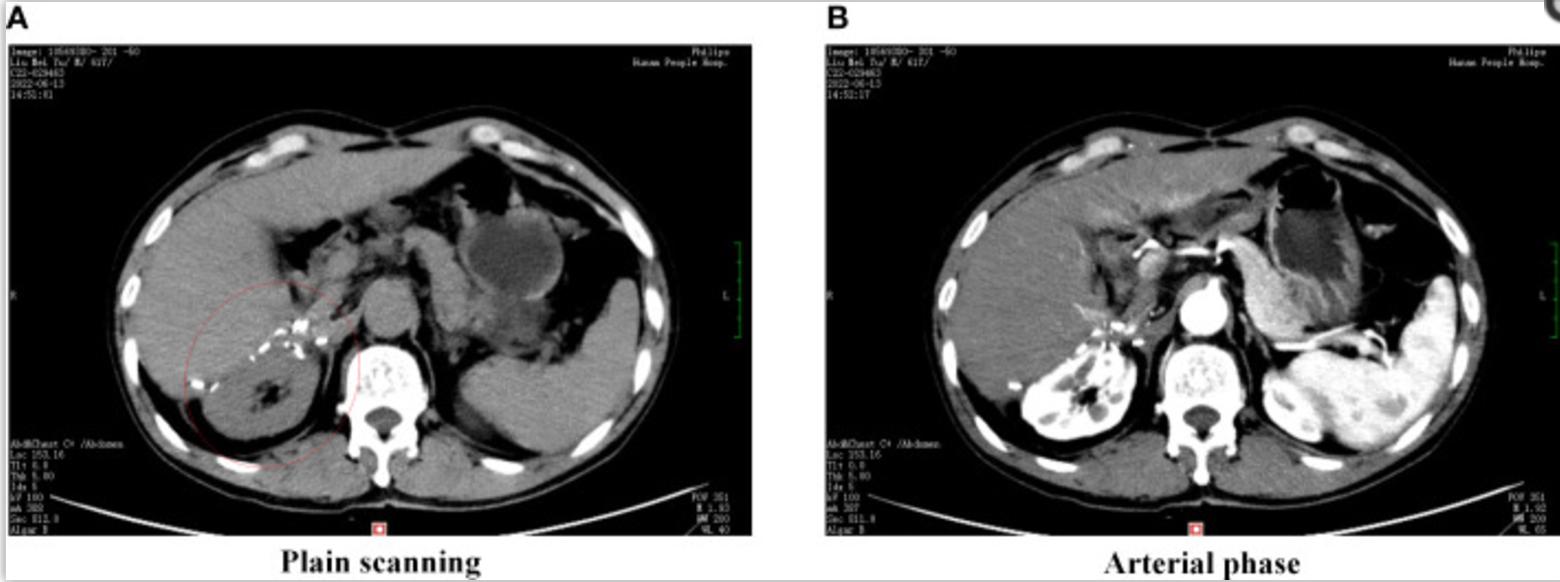

腹部增强CT显示腹膜后肿瘤(11.8×11.0×8.3cm)位于右肾上腺区,动脉期明显增强,静脉期持续增强(图1A、B)。磁共振成像(MRI)显示动脉期增强不均匀,肝胆期无异常信号灶(图1C、D)。在实验室测试中,由于肿瘤位于肾上腺区域,对血清钾、醛固酮、皮质醇和血浆肾上腺素进行了测试,结果正常。血清甲胎蛋白(AFP)和甲胎蛋白-L3%分别为23.69 ng/mL和82.1%。

图1 腹部增强CT及磁共振成像图